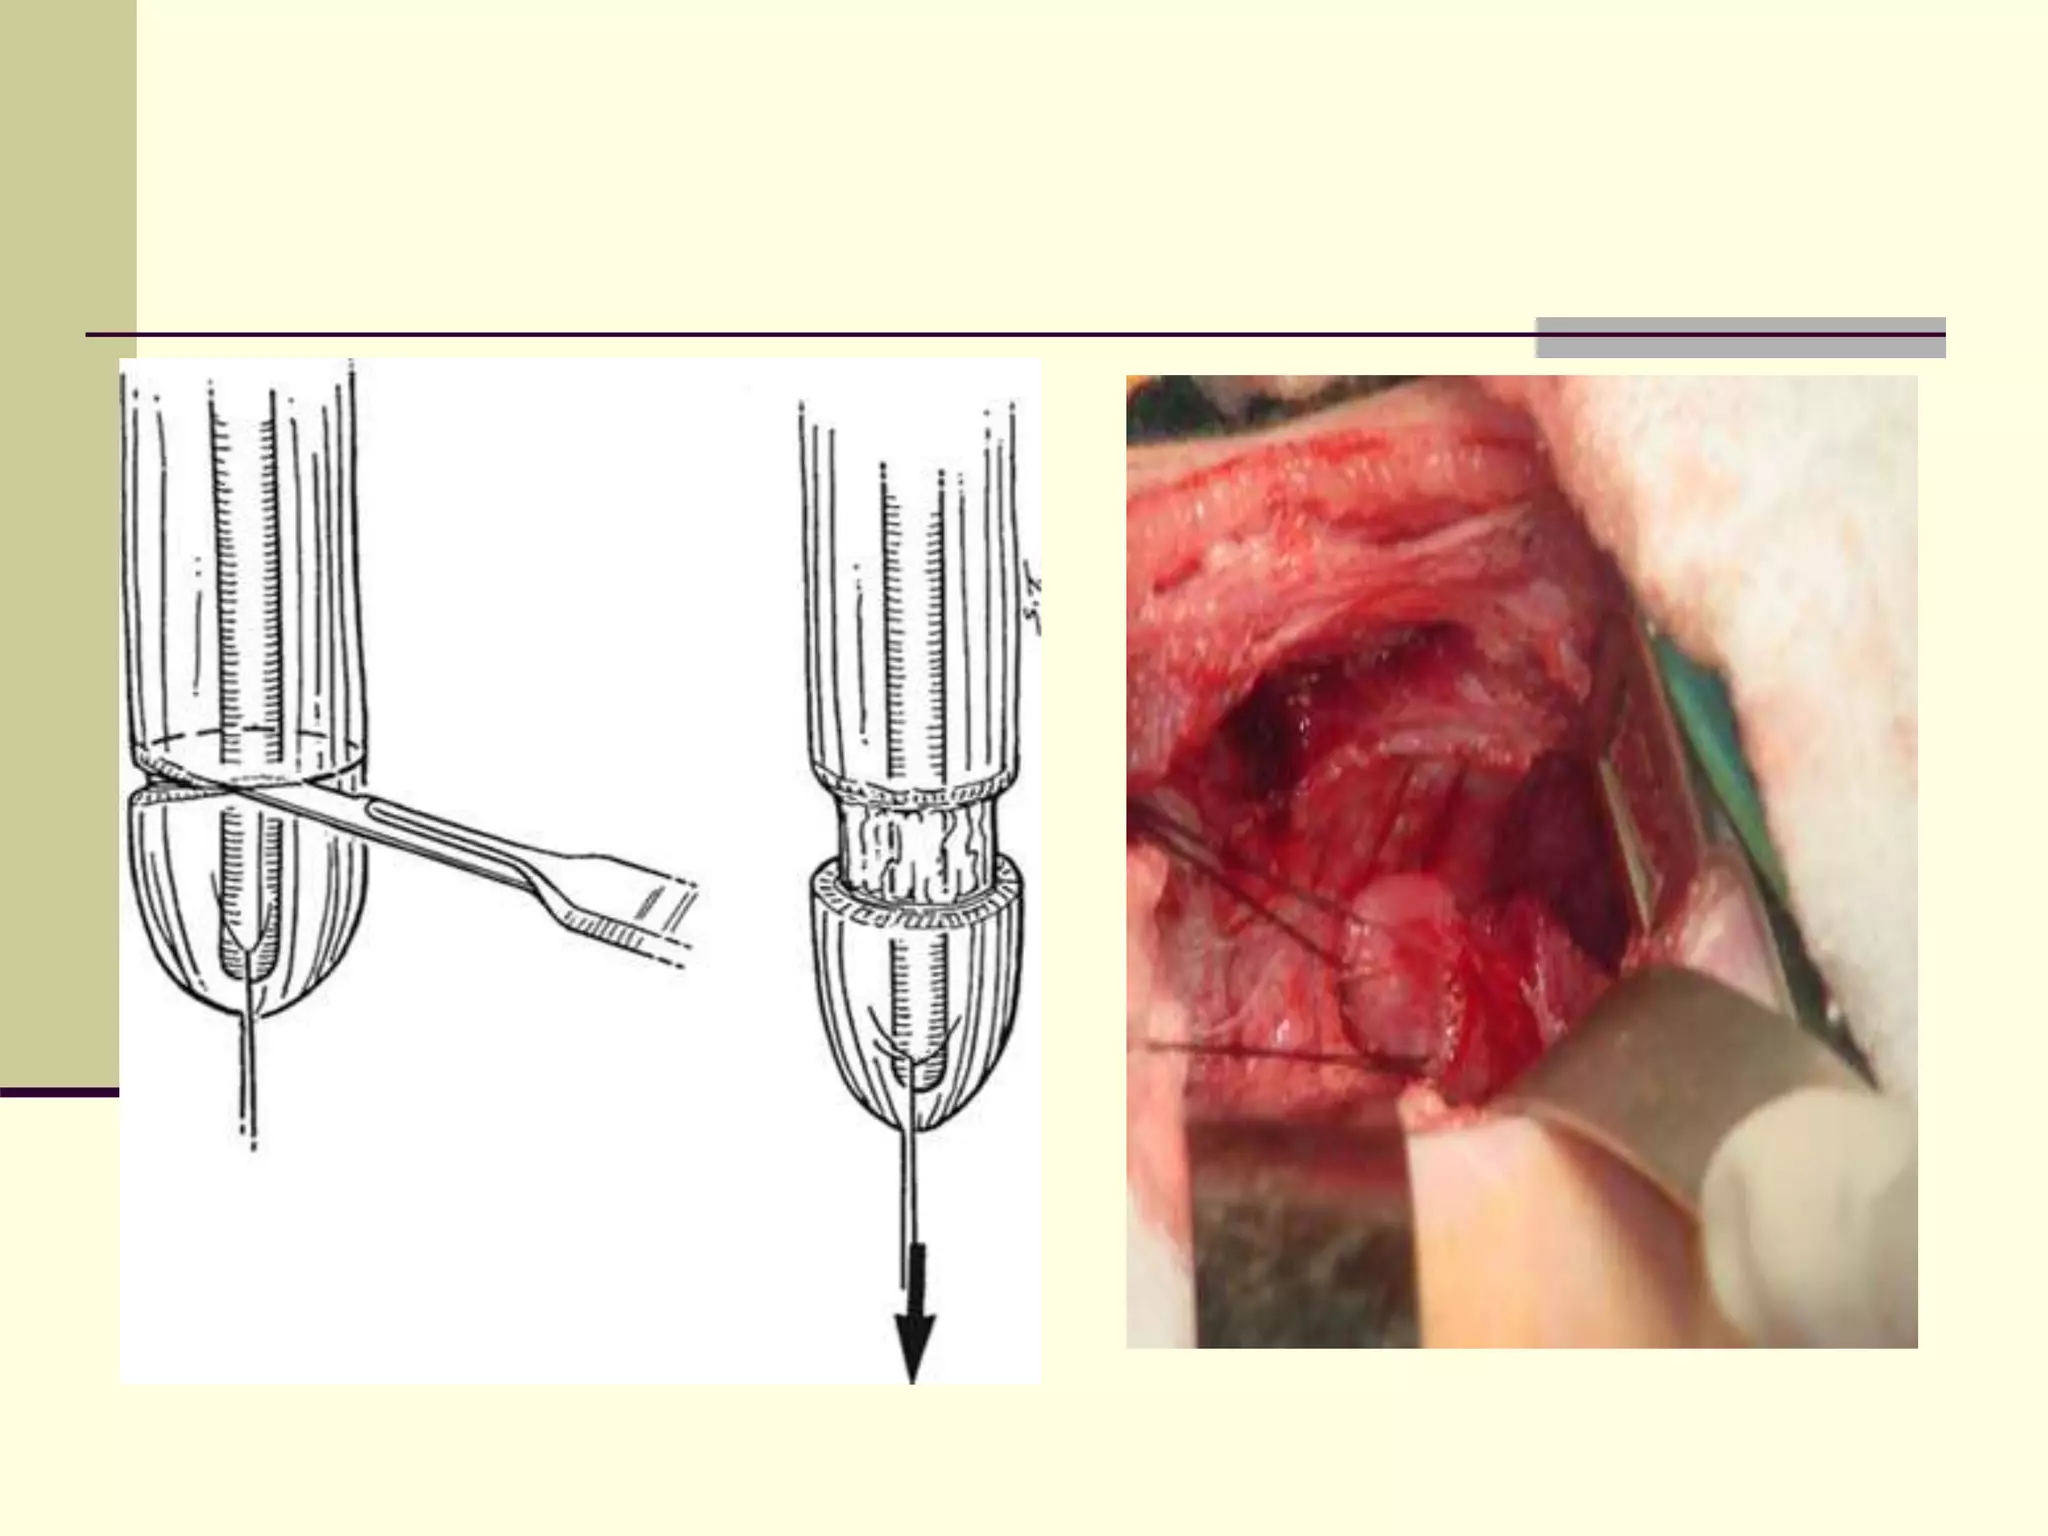

 A circular myotomy, as described by Livaditis,

can lengthen the proximal or distal end .

 The myotomy is performed approximately 2.0

cm above the blind proximal atretic end to

divide the longitudinal and circular smooth

muscle.

 This increases the length of the proximal

esophagus by approximately 1.0 cm and often

facilitates a primary anastomosis without

tension.

 Occasionally, a second myotomy may be

required at a more proximal level .

 A proximal spiral myotomy has been described

 Step ladder myotomy